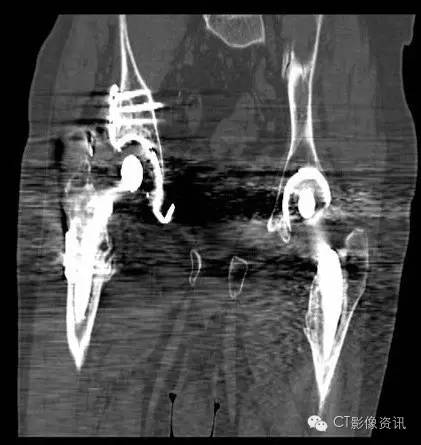

双侧髋关节置换术后

Without MAR

With MAR

Smart MAR 有效地消除了双侧髋关节置换术后的伪影,便于术后观察、复查等。